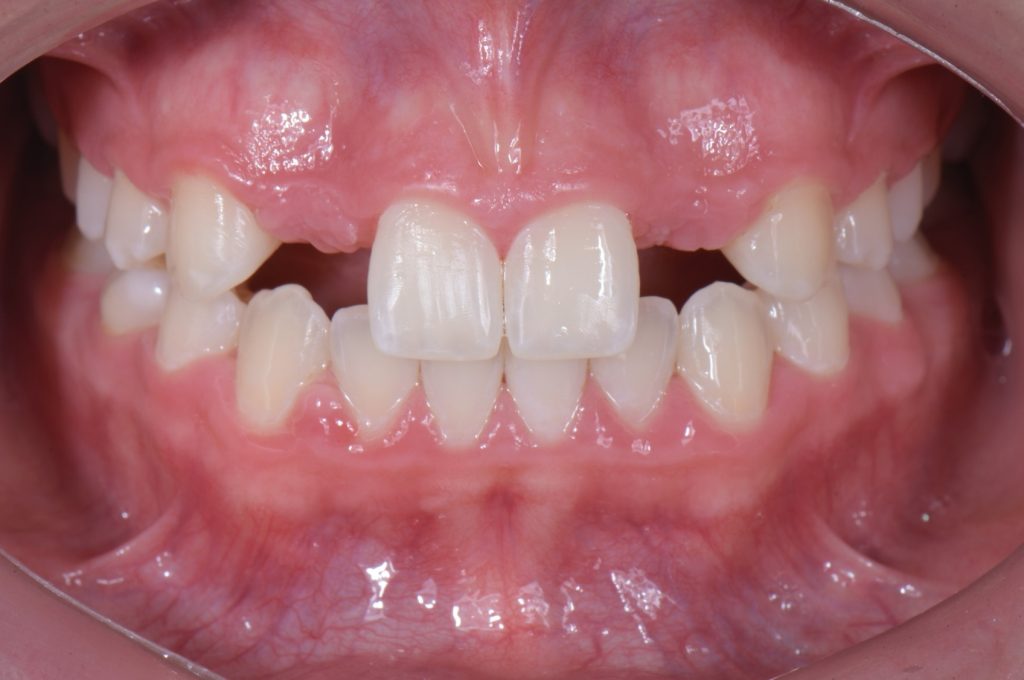

Solution #3: Cantilever Bridge

A fundamental principle in contemporary therapy is to conserve tooth structure by being as minimally invasive as possible. Today, doing a full-coverage restoration on intact natural teeth is extremely difficult to justify, but there are specific conditions where a cantilever bridge can be considered a choice solution.

In this case, a 16-year-old female (Figs. 13-23) presented with congenitally missing lateral incisors with significantly undersized canines that were out of occlusion. Both these specific features meant that from a functional and esthetic standpoint (tooth position and size), the canines required additional contour to attain a favorable occlusal contact and a more dominant contour, characteristic of a maxillary canine.

So, I needed to make sure that there was enough space for the restorative material. A purely additive wax-up was required to attain a mockup, verifying that the proposed contours were esthetically pleasing. This can be obtained either by an analogic approach (Fig. 15) or a digital approach (Fig. 16).

Incisally, there was no reduction required, the reduction was minimal, and from a cervical perspective, a 0.5 mm finish line was prepared (Fig. 17). This allowed our team to do a fundamentally additive design.

It is important here to emphasize that even if the age and preference of the patient allowed us to plan for an implant-supported restoration to replace the lateral incisors, the need to enhance the contours of the canines would still be required to provide a functional and esthetically pleasing result.

The undersized canines were out of function, removing all protective coverage for the lateral incisors. This provided a unique opportunity and indication for the most conservative scenario of a cantilevered RBFDP.

When considering a zirconia crown, we needed to ensure there was sufficient room for the wall thickness to be a minimum of 0.3 mm (ideally between 1.0 mm and 1.5 mm), an incisal reduction of 2.0 mm, and a visible and continuous circumferential chamfer with a reduction of at least 0.5 mm at the gingival margin. The patient’s preliminary condition allowed us to accomplish these space requirements with hardly any tooth reduction (Fig. 17).

RBFPD has an exceptional record, so this cantilever bridge can be considered a long-term solution. However, if in the future an implant-supported restoration is desired, the pontic of this cantilever can be removed, and an implant could be placed and restored.